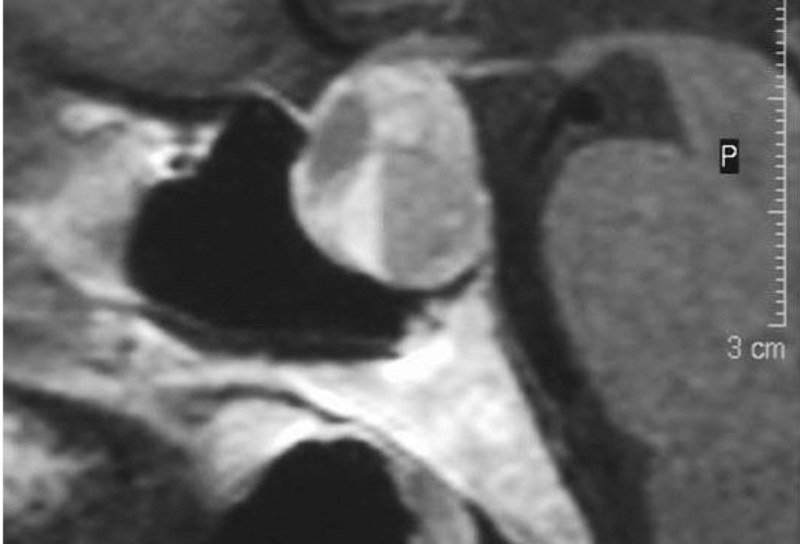

- Defectos quiasmáticos. El defecto típico de lesión quiasmática es una hemianopsia bitemporal heterónima. Si ésta es de predominio superior, la sospecha corresponde a lesiones que comprimen el quiasma desde abajo (ej. adenoma de hipófisis), y si es inferior, a lesiones supraquiasmáticas (ej. craneofaringioma), sin olvidar la posibilidad de quiasmopatías intrínsecas (tumorales o inflamatorias). En casos de larga evolución puede observarse la atrofia en banda o en pajarita en ambos discos ópticos. Si la hemianopsia se presenta de manera súbita, acompañada de cefalea intensa y/o náuseas y vómitos, u oftalmoparesia hay que descartar la apoplejía o ictus hipofisario. Se debe realizar una RM o TC craneal urgente ya que este proceso requiere tratamiento quirúgico inmediato (Figura 12).

.

Figura 12. Apoplejía hipofisiaria. Nivel de hiper/hipointensidad provocado por sangrado agudo (cuando el paciente está en decúbito)